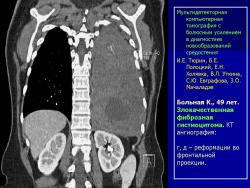

Средостение.  "Опухолевый рост".

Продолжение.